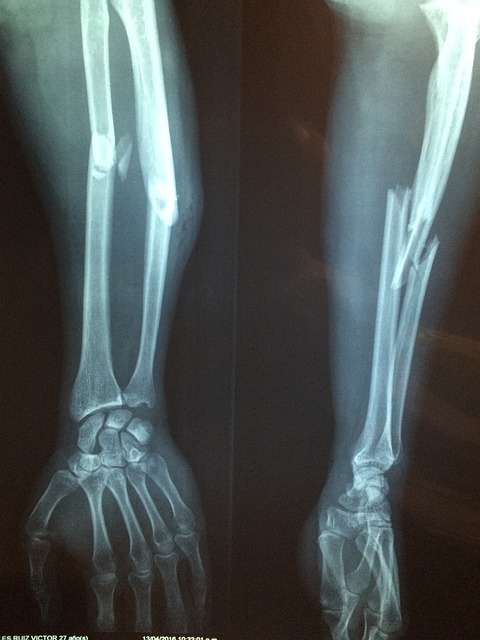

② 뼈가 잘 부러지고 전신이 쑤신다

폐경 이후에는 골다공증이 잘 오는데 여성호르몬이 뼈를 잘 유지시키는데 호르몬이 떨어지고 안 움직이다 보니까 전신이 쑤시고 하는 증상이 생길 수가 있습니다.

3. 골다공증과 골절이 올 수 있다

폐경 이후에 여성호르몬이 급격히 낮아지면 여성호르몬이 하고 있던 역할 중 하나가 난소에서 나와서 뼈에 작용해서 뼈를 만들고 있는 조골세포에 작용을 해서 뼈를 유지하고 있었는데 그 기능이 갑자기 없어지는 것입니다. 결국은 뼈의 생성을 돕는 여성호르몬 농도가 낮아지면 뼈를 파괴하는 파골세포 활성이 늘면서 골다공증이 발생하고 심하면 골절이 오기도 합니다. 그리고 남성호르몬도 천천히 낮아지고는 있지만 나중에 혹시라도 음주와 흡연의 빈도가 높아지면 뼈의 손실은 더 빠르게 증가합니다.